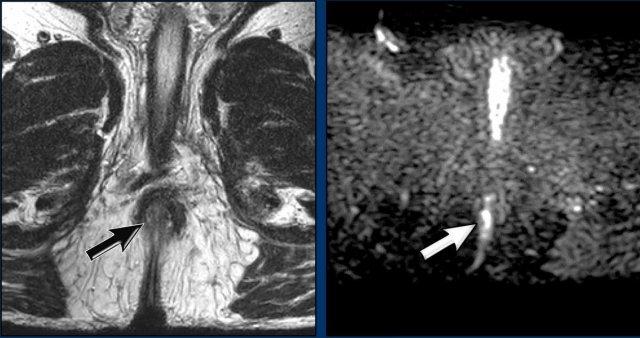

Hình ảnh

Khối u (mũi tên) trước điều trị kèm hạch mạc treo trực tràng nghi ngờ.

Giai đoạn: cT2N1a.

Tái phân giai đoạn

Sau điều trị, khối u đã giảm kích thước.

Không còn khối tín hiệu trung gian tồn dư trên các chuỗi xung T2W mặt phẳng đứng dọc và ngang.

Chỉ còn một vùng xơ hóa giảm tín hiệu nhỏ

(mũi tên).

Điểm tối nhỏ trên bản đồ ADC biểu hiện hiện tượng ‘xuyên tối’ do xơ hóa (mũi tên).

Có thể phân biệt hiện tượng này với hạn chế khuếch tán thực sự, vì không có tín hiệu cao tương ứng trên hình ảnh khuếch tán giá trị b cao.